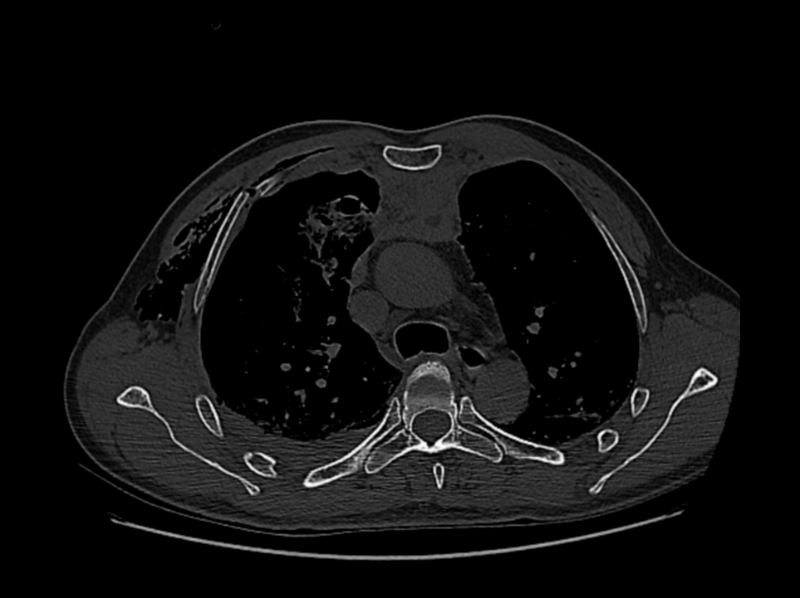

△治療后

手術(shù)當(dāng)日,王蕓帶領(lǐng)團(tuán)隊實施為薛先生手術(shù),先對右上肺、右下肺破裂傷進(jìn)行細(xì)致修補(bǔ),保障肺部功能恢復(fù);隨后開展右側(cè)第3-8肋骨骨折切開復(fù)位內(nèi)固定術(shù),憑借熟練操作完成骨骼精準(zhǔn)復(fù)位與固定;面對開胸后的出血,團(tuán)隊快速找到出血點并妥善止血。整個手術(shù)過程中,各環(huán)節(jié)銜接緊密,憑借醫(yī)護(hù)團(tuán)隊成熟的手術(shù)技術(shù)和豐富的臨床經(jīng)驗順利為薛先生完成手術(shù)。